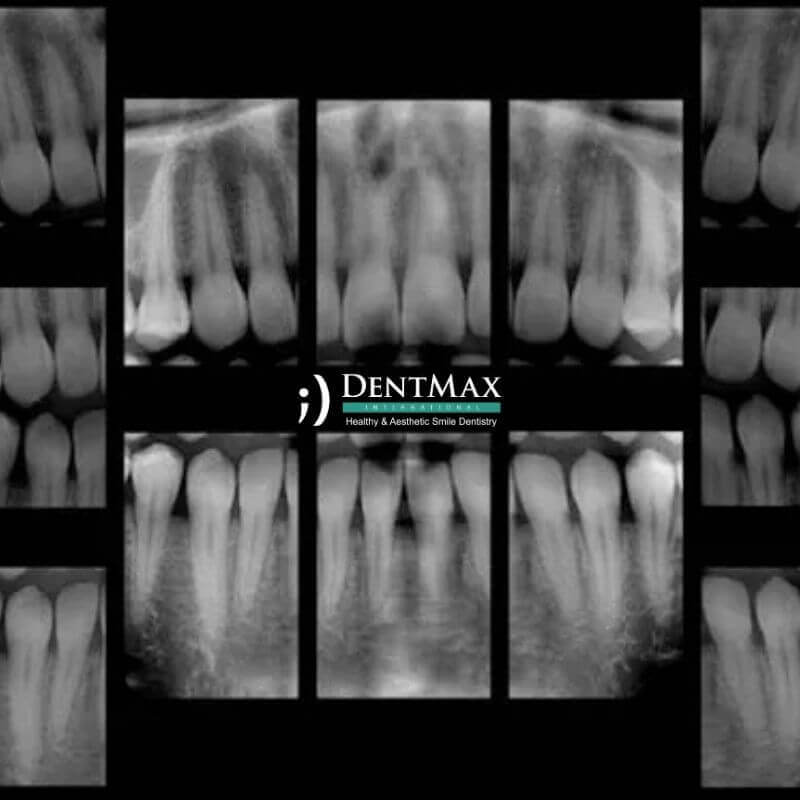

Periapikal röntgen, dişin kök yapısı ve çevre dokularının ayrıntılı şekilde görüntülenmesini sağlayan, tanı koymada kritik rol oynayan bir dental görüntüleme yöntemidir. İstanbul’daki DentMax Diş Kliniği olarak, periapikal röntgeni gelişmiş dijital sistemlerle uygulayarak, çürükler, apseler, kist oluşumları, kanal tedavisi öncesi ve sonrası durumlar gibi birçok durumu detaylı şekilde değerlendirmekteyiz. Bakırköy, Kadıköy, Şişli ve çevresinden gelen hastalarımızın teşhis sürecini hızlandırmak ve kesin tanılar koymak için bu yöntemi güvenle kullanıyoruz.

Dijital Periapikal röntgen (RVG), bir veya birkaç dişin kök ucunu ve çevresindeki kemik dokuyu detaylı şekilde gösteren intraoral (ağız içi) bir röntgen türüdür.

Küçük bir sensör veya film ağız içine yerleştirilir. X-ray cihazı ile hedeflenen diş bölgesi çekilir. İşlem yalnızca birkaç saniye sürer ve ağrısızdır.

Kanal tedavisi öncesi ve sonrası, kök enfeksiyonları, kemik kaybı, apse, kist şüphesi, çürüklerin derinliğini tespit gibi durumlarda gereklidir.